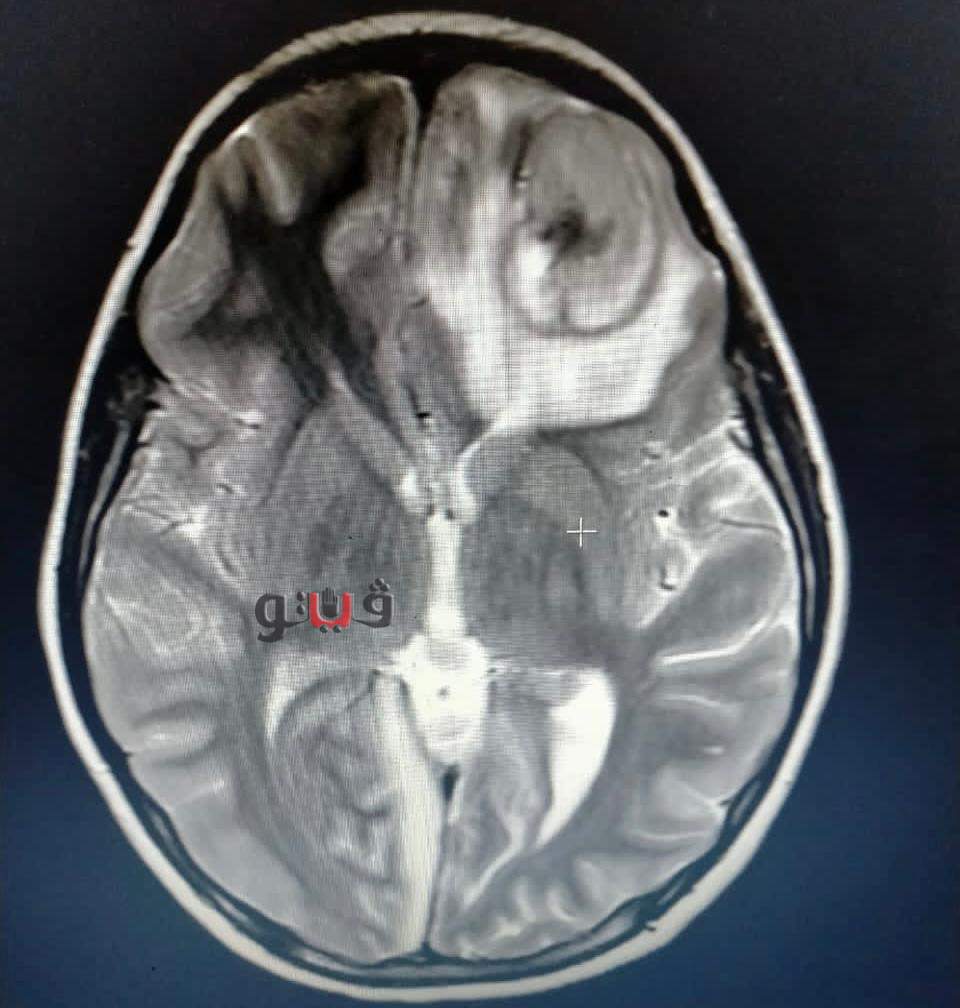

وأكد مدير مستشفى الأطفال أن الطفلة جاءت إلى المستشفى والتشخيص لحالتها كان في البداية غير مفهوم ولكن بعد الفحوصات وتشكيل فريق طبي، وعمل رنين تبين أن الطفلة لوما تعاني من ٢ خراج على المخ وخراج على الرئة وتسمم في الدم .

وقال مدير مستشفى الأطفال: الحمد الله اجتهادنا كفريق طبي مكون من الدكتورة ميادة عاطف، تخصص أمراض معدية وفريق من الجراحين قام بتفريغ الصديد من المخ وخرجت لوما من المستشفى، والحمد لله كتب الله لها الشفاء.